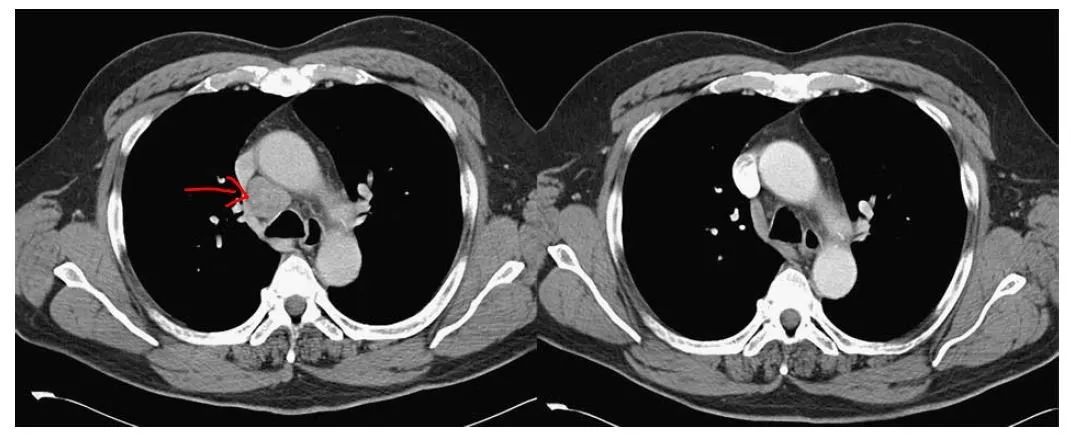

半氧化锗治疗肺梭形细胞癌完全缓解一名47岁女性因呼吸短促和咳嗽入院 。 她身体一直很好 , 直到5个月前 , 她发现左肺区域有轻微症状 。 胸部CT示左肺不张 , 肿物3.4×3×4.5 cm 。

患者接受了两个周期的美司钠、阿霉素、异环磷酰胺和达卡巴嗪治疗 , 但是症状出现恶化 , 有肿瘤进展的影像学证据 。 患者选择停止所有治疗 。

患者开始使用相同的方案(二倍半氧化二羧乙基锗 , 7.2 g / d , 然后逐渐减少药物)每日自我用药 。

【家属说|「案例」10例晚期癌症患者达完全缓解!这些治疗方案创造奇迹】5个月和7个月胸部CT扫描显示胸部肿块几乎完全消失 。 在初步诊断4年后 , 该患者仍无复发的迹象 , 并继续服用低剂量倍半氧化锗 。 病人否认她的治疗有任何明显的副作用 。